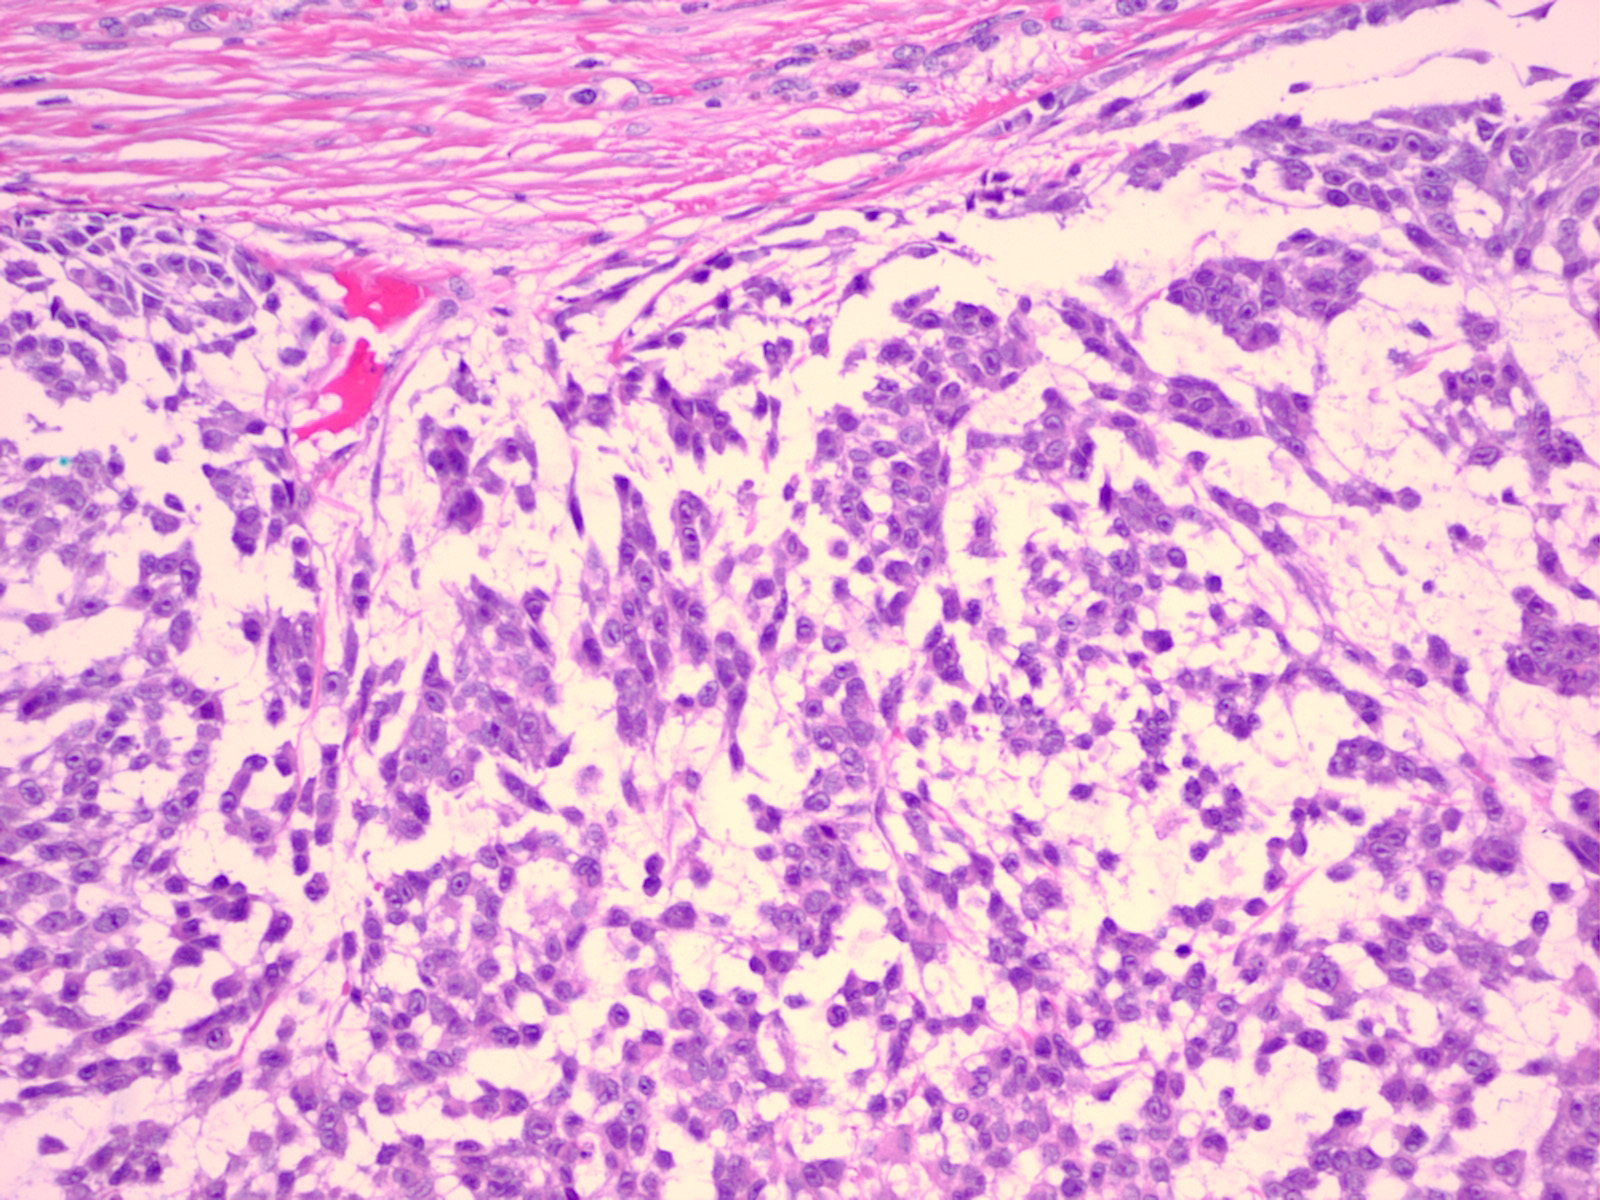

melanoma_mucinous